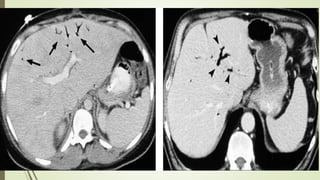

TC + C

Secundaria

 Distribución en banda o lineal del

aire en la pared del intestino

afectada.

 Forma lineal o curvilínea.

 Etiología isquémica: dilatación de la

luz intestinal (íleo), engrosamiento

parietal, realce anormal.

 Neumoperitoneo o neumorretroperitoneo.

 Gas en venas mesentéricas o portales.

 El gas biliar se concentra en los conductos centrales cerca de la porta hepática.

 ± trombosis arterial o venosa mesentéricas

 TCMD con ventana para pulmón, con el fin de detectar el gas intramural y venoso

Protocolo recomendado

 TCMD con contraste Lv. a 3-4 ml/s y colimación de 1,5-3 mm

 35 segundos de retraso para la adquisición de imágenes y se repite en fase venosa

pasados 80 segundos

 El agua como contraste oral facilita la angiografía porTC

 Reformateos multiplanares para la angiografía por TC

• #81 Abdominal CT images show free air ( long arrows ) and small-bowel PI ( short arrows, C) but also hepatic portal venous gas (arrowheads B ) not seen on radiograph. At surgery, diffuse ischemia of small bowel was found. Patient died 1 week late.